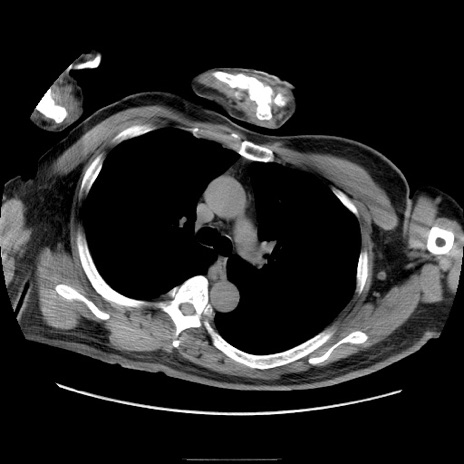

症例22(横断像)

【症例】50歳代男性

【主訴】腹痛

【現病歴】AVMからの被殻出血のため回復期リハ病棟入院中。 本日午後3時頃急に下腹部痛が出現した。

【既往歴】AVM、被殻出血、虫垂炎、高血圧

【身体所見】意識晴明、左半身不全麻痺、会話の理解は良好、36.5°C、腹部:膨隆、全体に板状硬、下腹部正中に圧痛点あり、反跳痛-、筋性防御不明、右下腹部にope scar

【データ】WBC 9400、CRP 0.06